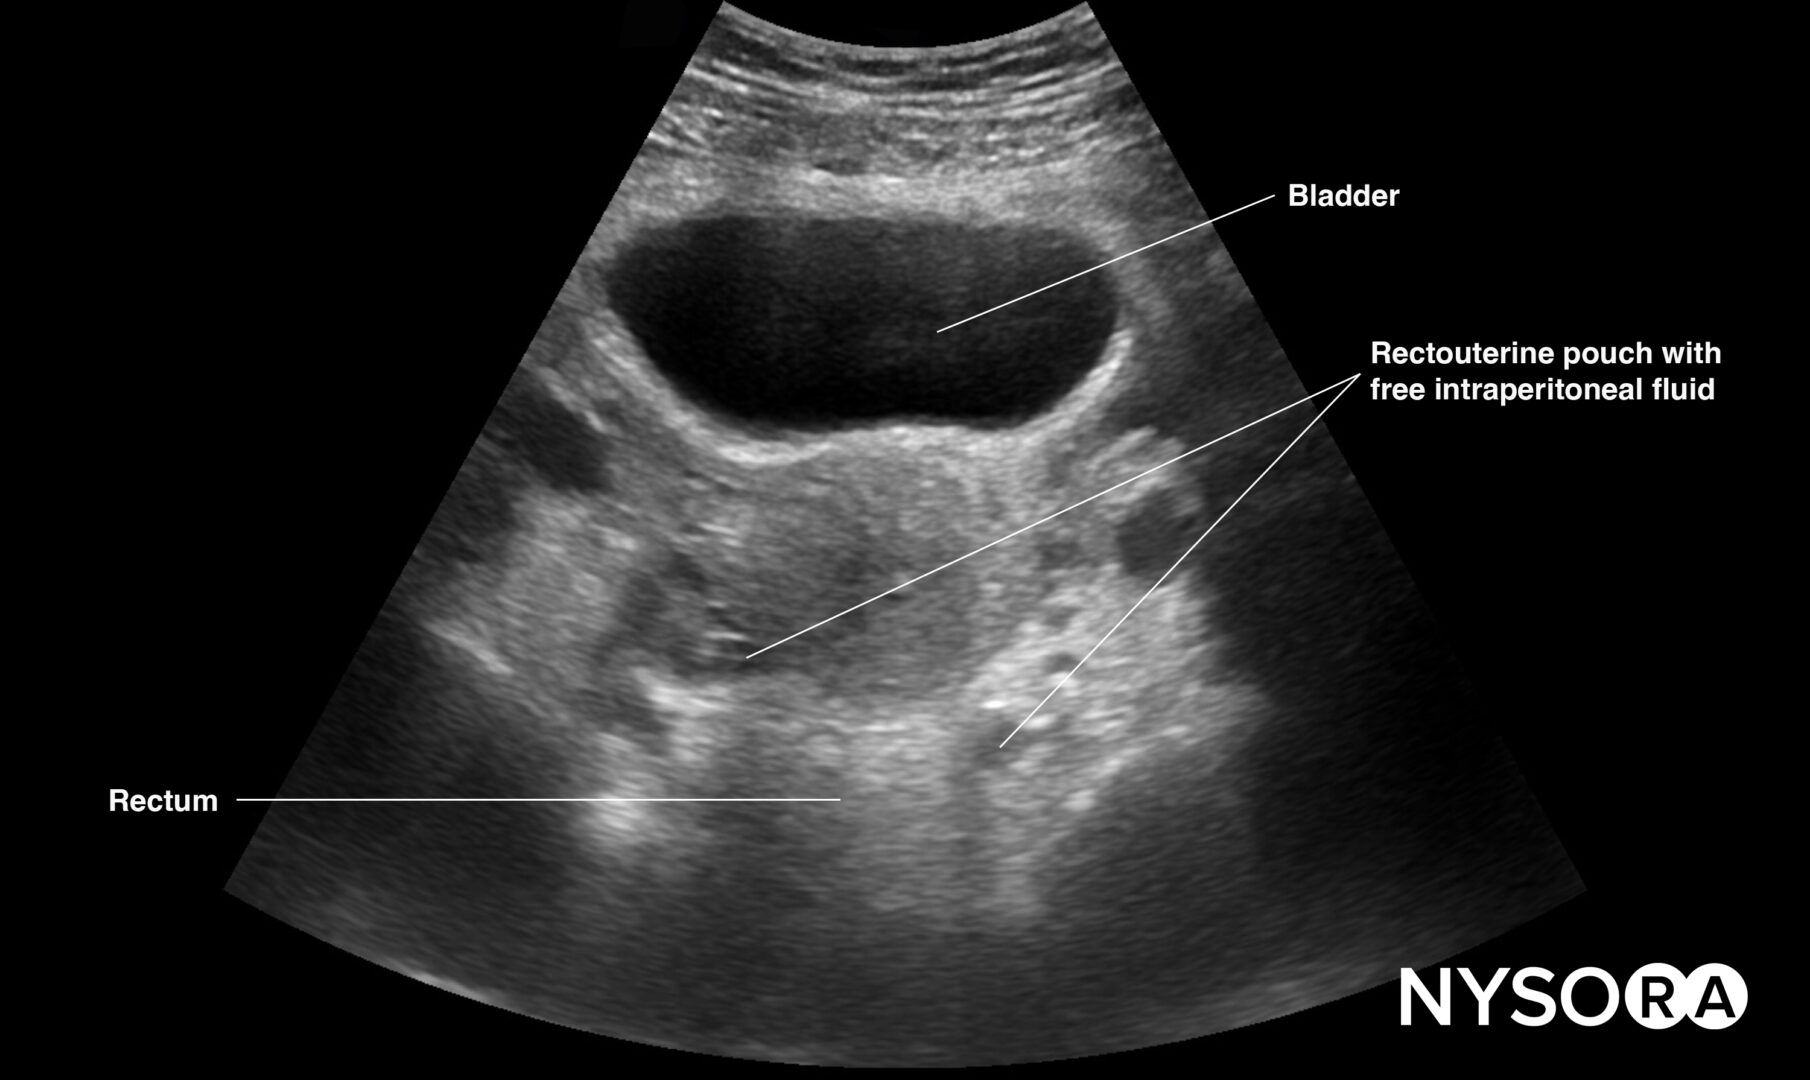

Pelvic free fluid collects behind the bladder or the area lateral to the bladder (rectovesical pouch in men and the rectouterine pouch or pouch of Douglas in women).

Sonoanatomy of interest in females:

Transverse view of the female pelvis with free fluid in the rectouterine pouch.